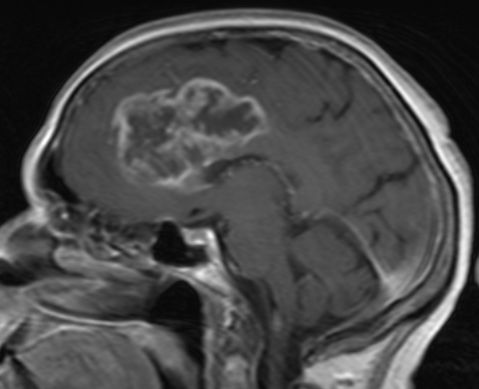

36-jähriger Mann, der vor 7 Jahres ein rechts-frontales Astrozytom Grad II mit Übergang in ein anaplastisches Astrozytom III hatte.![]() |

Jetzt Krampfanfall. Das MRT zeigt ein großes frontales Schmetterlingsgliom.![]() | |||

Die MRT-Kontrolle mit KM vor einem Jahr zeigt eine unauffällige Resektionshöhle.![]() |